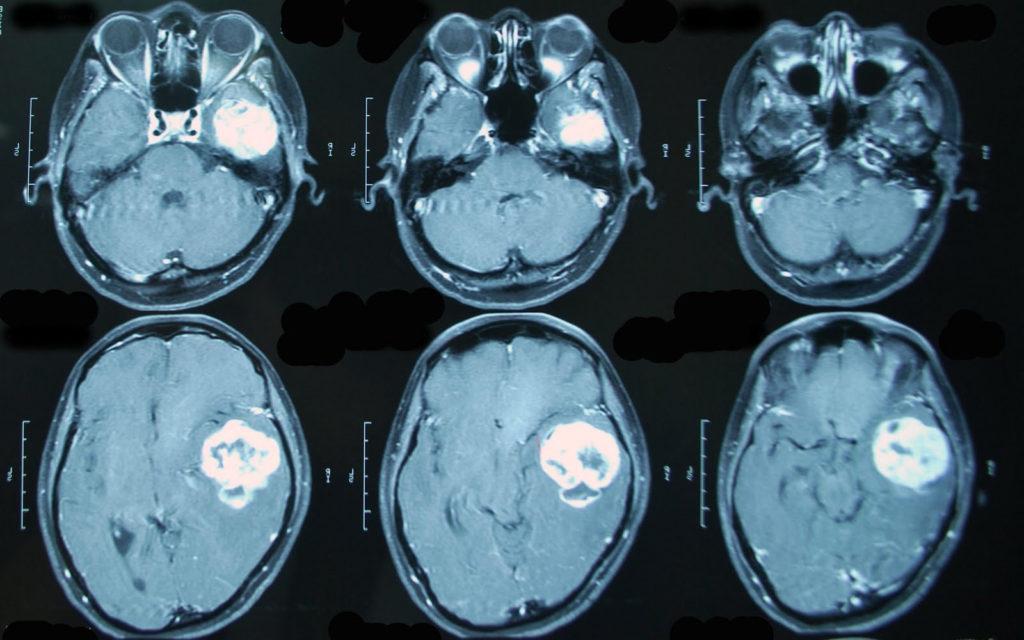

- МРТ спинного столба, головного мозга (помогает определить топографическую стадию патологии);

- компьютерная томография (дает возможность определить кальцификаты нейробластомы и характер новообразования).